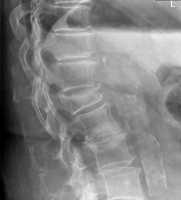

Möglichkeiten der direkten Zementinjektionstechnik bei Wirbelkörperfrakturen - Drei Fallbeschreibungen der Radiofrequenz-Kyphoplastie (RFK) mit ultrahochvikösem Knochenzement